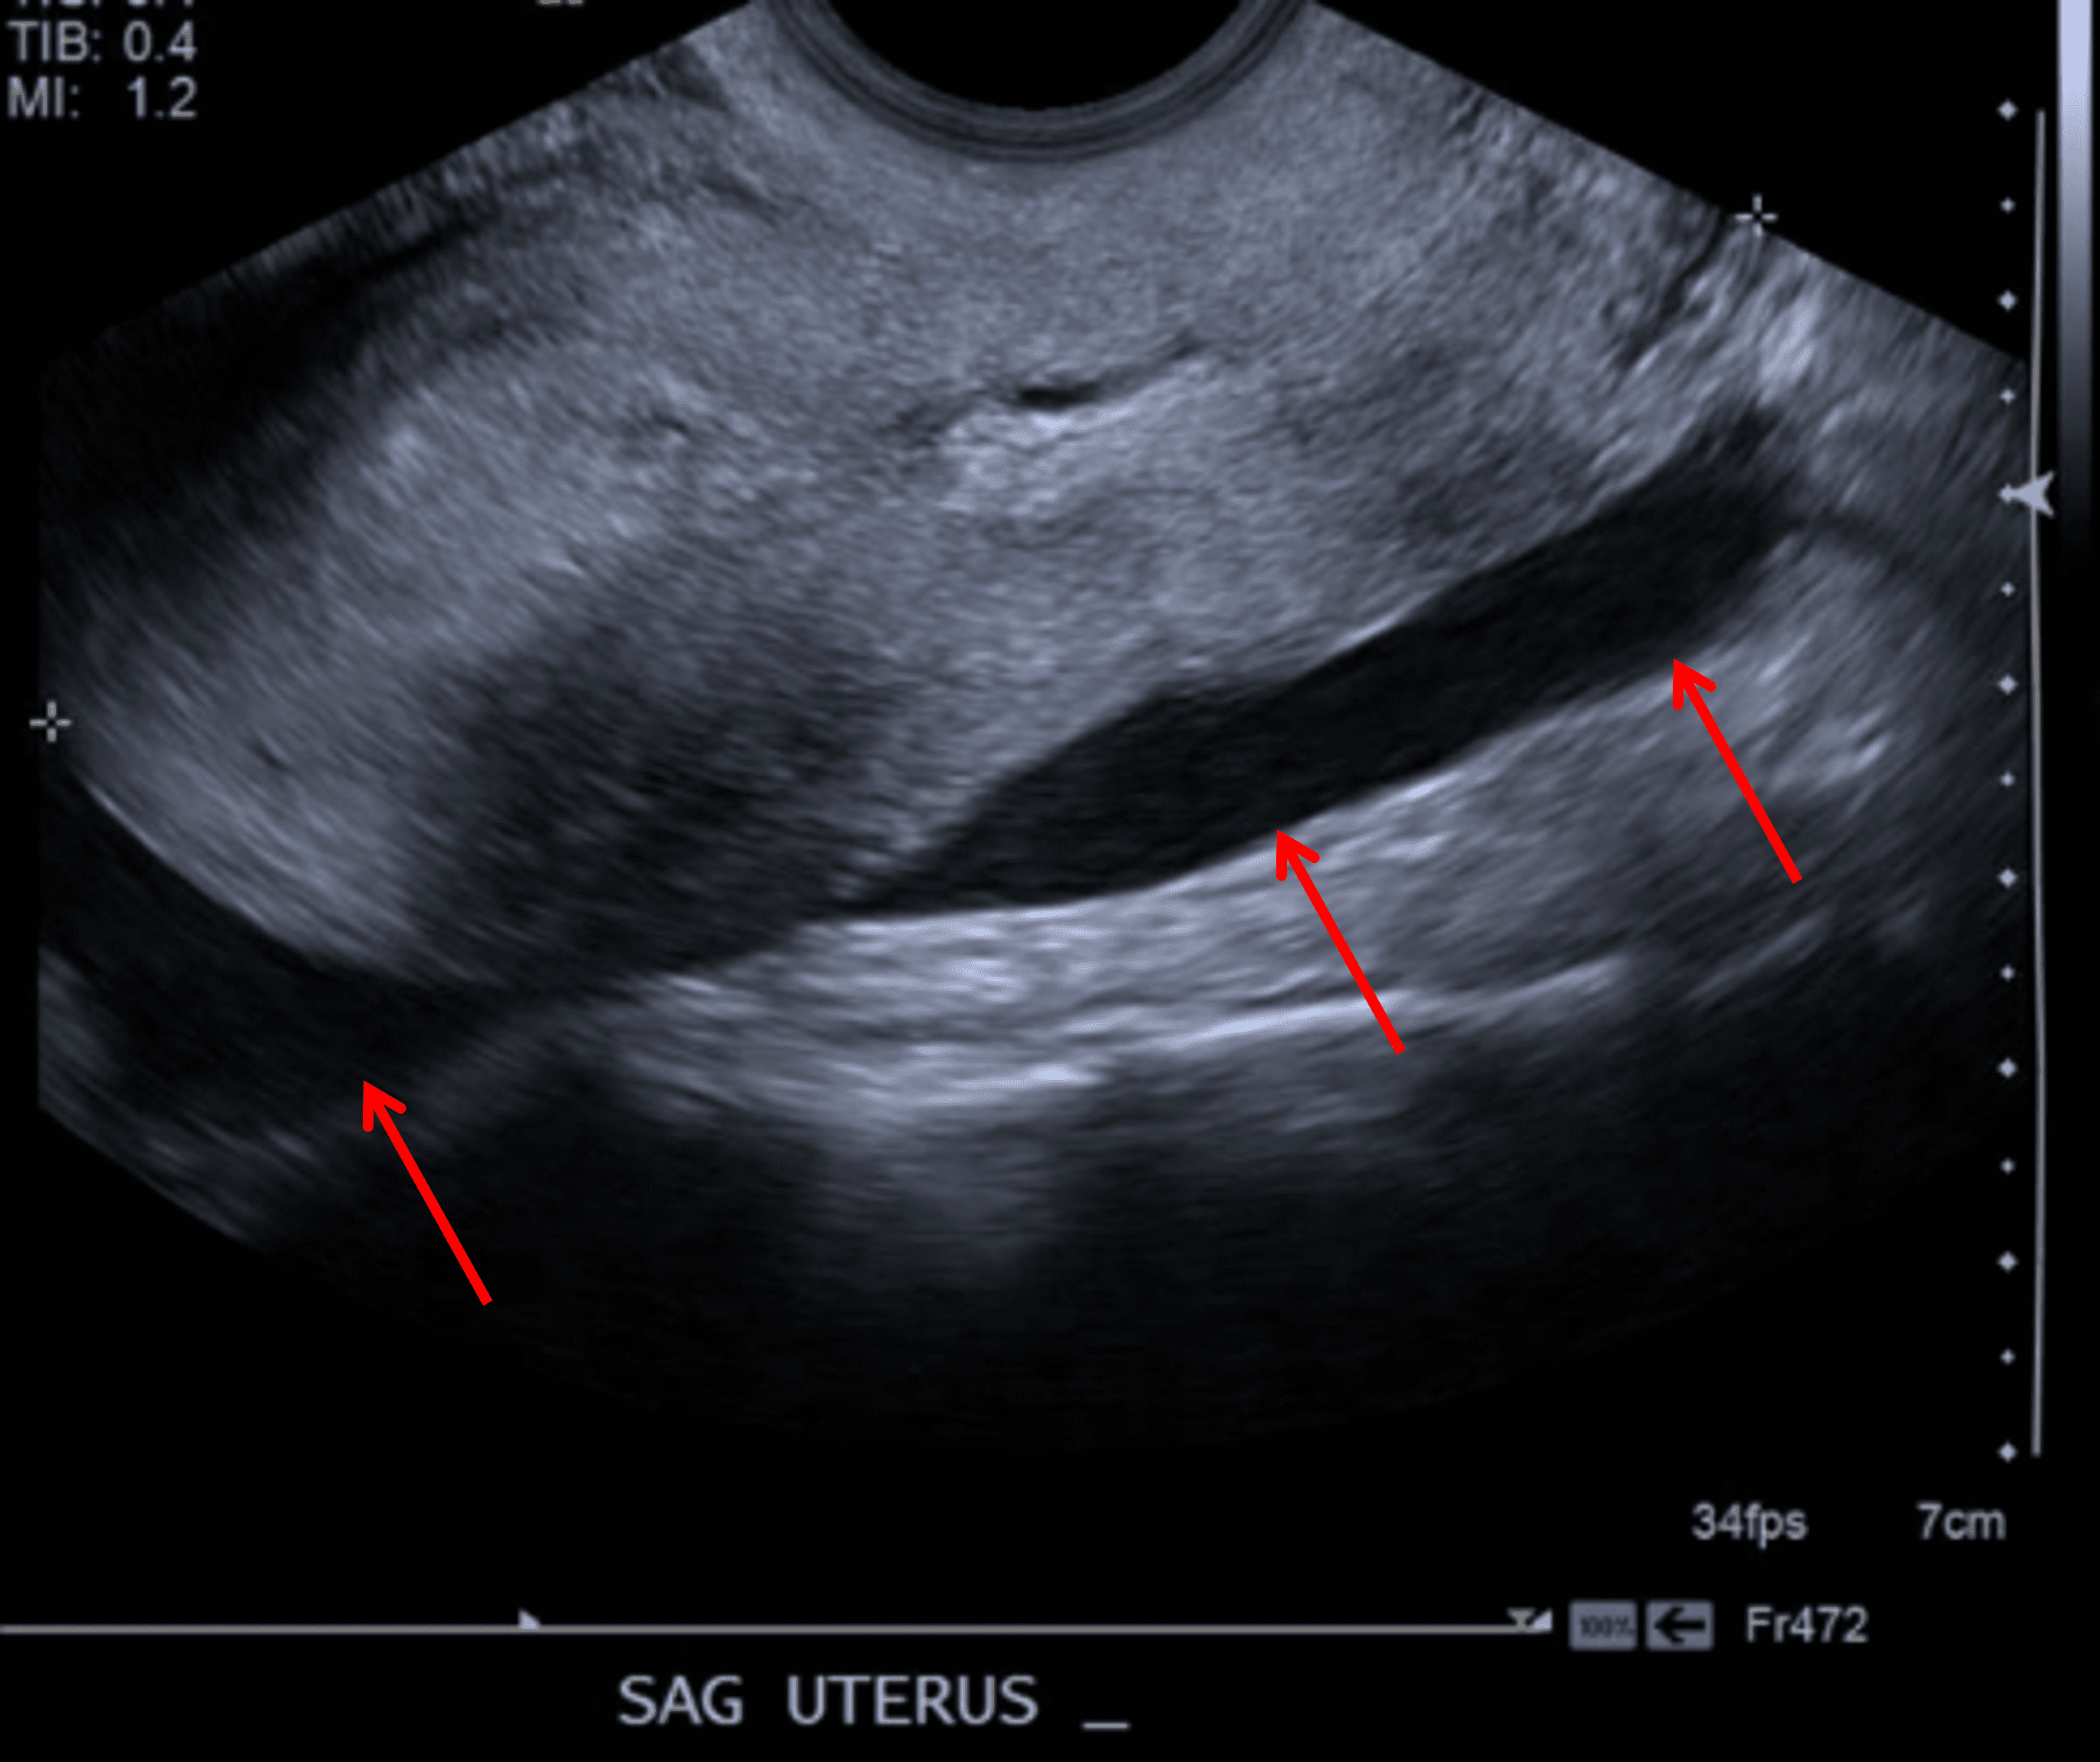

Age: 26

Sex: Female

Indication: Lower abdominal pain

Negative pregnancy test

Ruptured ovarian cyst

Sample ReportNo evidence of ovarian torsion.

Moderate to large volume free fluid layering in the pelvis with internal echoes, likely representing hemoperitoneum.

Simple appearing right ovarian cyst measuring up to 6.5 cm. Given size, recommend followup pelvic ultrasound in 6-12 weeks for further assessment.